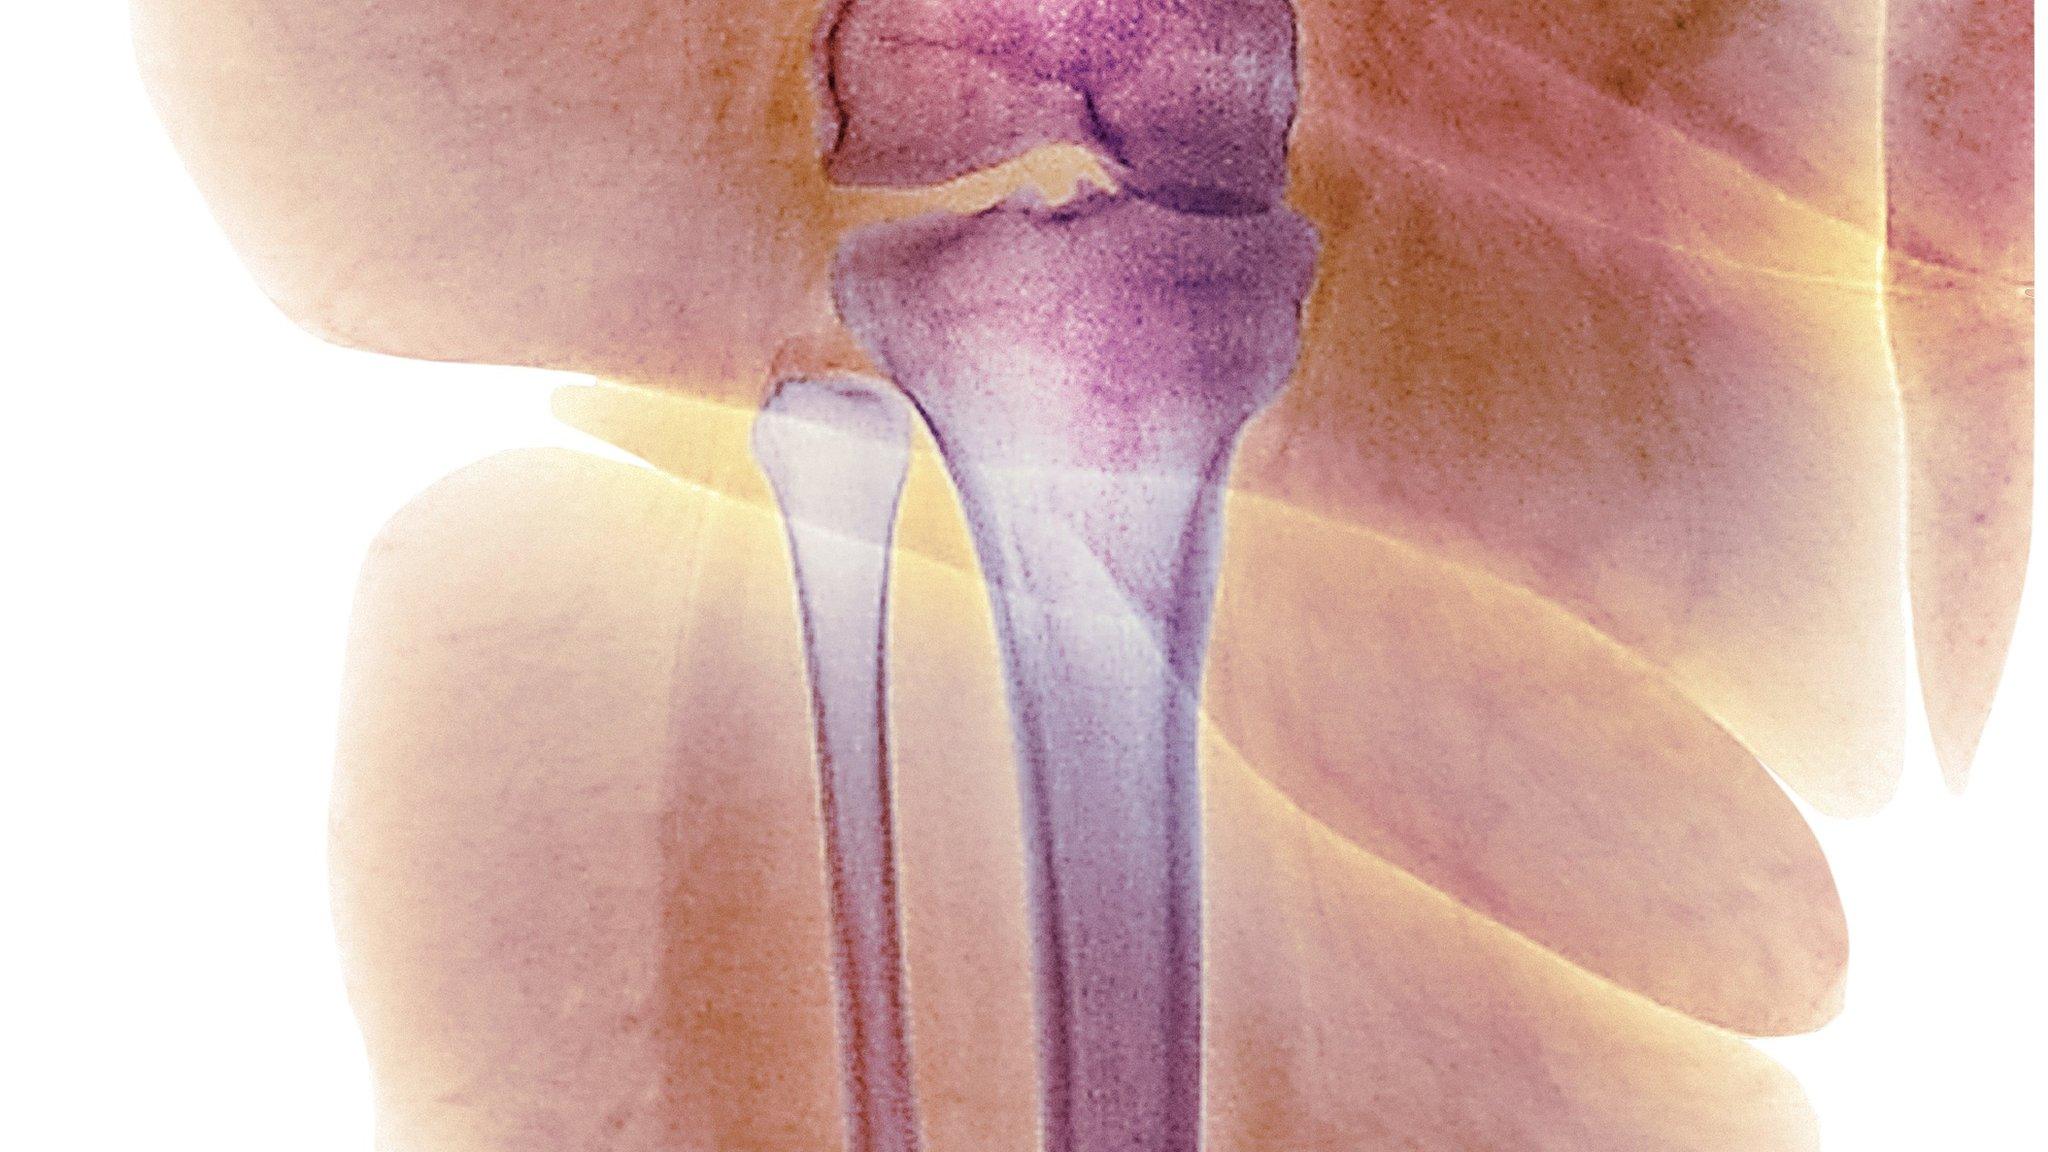

Scientists hope their findings could help to treat common forms of osteoporosis

A discovery in mice could help to treat people with a form of brittle bone disease, scientists said.

One in 15,000 people in the UK are estimated to have osteogenesis imperfecta (OI). It is an inherited condition, where abnormalities in the genes controlling collagen affect the bone's strength.